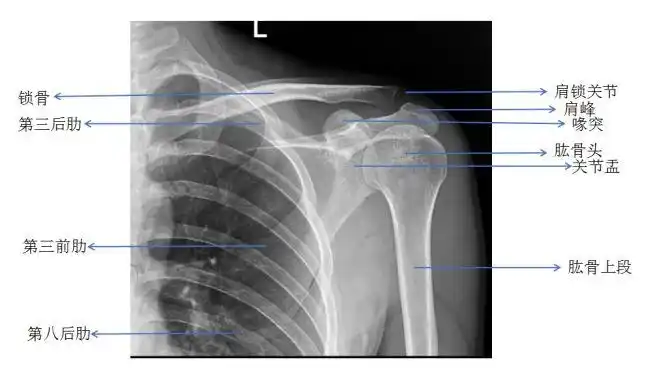

医学图文科普(肩关节),#医学科普 #每天跟我涨知识 #关节 - 抖音